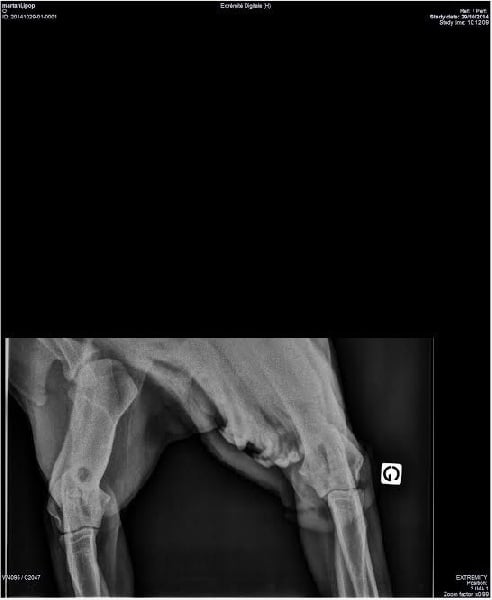

SCAU : Mention TRES BIEN radios des coudes : HD/A radios des hanches : HD/A |